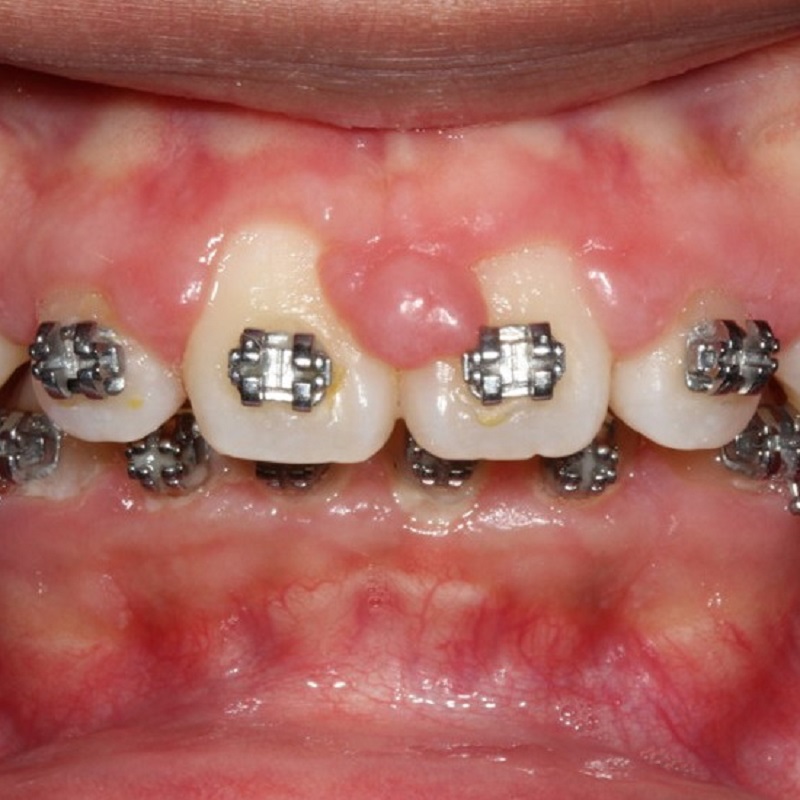

Durante el tratamiento de ortodoncia es común la deformación de la encía, con la cirugia de gingivectomia y gingivoplastia se remodela la encía corrigiendo tamaño y forma consiguiendo un contorno gingival más estético.

• Contorneado estético de encía con bisturí